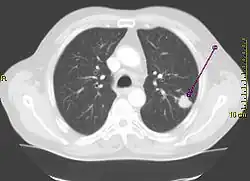

Tumoare pulmonară (marcată cu săgeată) vizibilă la radiografia toracică | |

Efectuarea unei radiografii toracice reprezintă unul dintre primii pași necesari pentru a investiga dacă o persoană prezintă simptome care pot sugera prezența cancerului pulmonar. Această radiografie poate arăta o masă evidentă, o extindere a mediastinului (sugerează răspândirea în nodulii limfatici), atelectazie (colabare), consolidare (pneumonie) sau revărsat pleural.[5] Imagistica prin computer tomograf este de obicei folosită pentru a oferi mai multe informații cu privire la tipul și gradul de extindere al bolii. Bronhoscopia sau biopsia ghidată CT este adesea folosită pentru a preleva mostre din tumoare pentru histopatologie.[13]

Cancerul pulmonar se prezintă, de cele mai multe ori, ca un nodul pulmonar solitar în cadrul unei radiografii toracice. Cu toate acestea, diagnosticul diferențial este extins. Multe alte boli pot să prezinte aceleași simptome, inclusiv tuberculoza, infecțiile fungice, cancerul metastatic sau pneumonia organizată. Printre cauzele mai puțin comune ale nodulului pulmonar solitar se numără hamartomul, chisturile bronhogenice, adenoamele, malformația arterio-venoasă, sechestrarea pulmonară, nodulii reumatoizi, granulomatoza Wegener sau limfomul.[45] Cancerul pulmonar poate fi, de asemenea, descoperit incidental, sub forma unui nodul pulmonar solitar la nivelul unei radiografii toracice sau tomografii computerizate realizate din alte motive.[46] Diagnosticul definitiv de cancer pulmonar are la bază examinarea histologică a țesutului suspectat în context clinic și radiologic.[4]